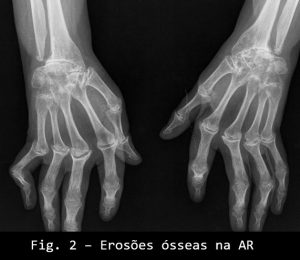

O osso é envolvido com aparecimento de erosões ósseas (visíveis ao rx) (ver figura 2 e 3) e que podem confluir e atingir grandes proporções). A presença de osteopenia é característica nos casos moderadamente avançados e nos doentes submetidos a longos períodos de terapia com corticoesteroides.